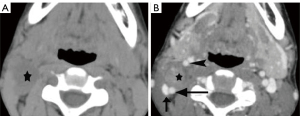

Schwannomas are benign tumors arising from Schwann cells surrounding peripheral nerves. Schwannomas in the carotid space most commonly stem from the vagus nerve. The tumor is usually a sharply demarcated round or oval mass with hypo-, iso-, or hyper-attenuation. Cystic degeneration, xanthomatous change, or areas of relative hypocellularity adjacent to densely cellular or collagenous regions usually contribute to heterogeneity of the tumor (Figure 1) (9,10). Schwannomas are hypovascular tumors, but in dynamic scans, they can show marked enhancement due to pooling of contrast agent resulting from poor venous drainage (11). More often, schwannomas demonstrate a variable degree of enhancement, most commonly patchy enhancement (Figures 2-7).

Due to its location between the vein and artery in the carotid space, schwannomas of the vagus nerve tend to separate the artery and vein, usually displacing the CCA/ICA medially and the IJV laterally (Figures 2,3) (12). Some schwannomas of the vagus nerve may displace the IJV and ICA/CCA in a posterior direction without splaying them and there is usually separation between the artery and vein (Figure 4). The cervical sympathetic chain runs in a fascial reflection posterior and slightly medial to the carotid space. Hence, schwannomas of the sympathetic chain tend to displace the IJV and CCA/ICA together, usually anteriorly and laterally (Figure 5) (5). A large schwannoma of the sympathetic chain may distort the surrounding anatomy and result in a posterior displacement of the carotid vessels without separation of the artery and vein (Figure 6) (13,14). Occasionally, a schwannoma of the cervical sympathetic chain may splay the internal and external carotid arteries at the carotid bifurcation but without encasing the arteries (Figure 7) (5). In these regards, the position of the tumor relating to the vessels in the carotid space is more important than the direction of vascular displacement. There has also been a reported case of schwannoma arising from the glossopharyngeal nerve in the carotid space causing posterior displacement of the ICA (15).